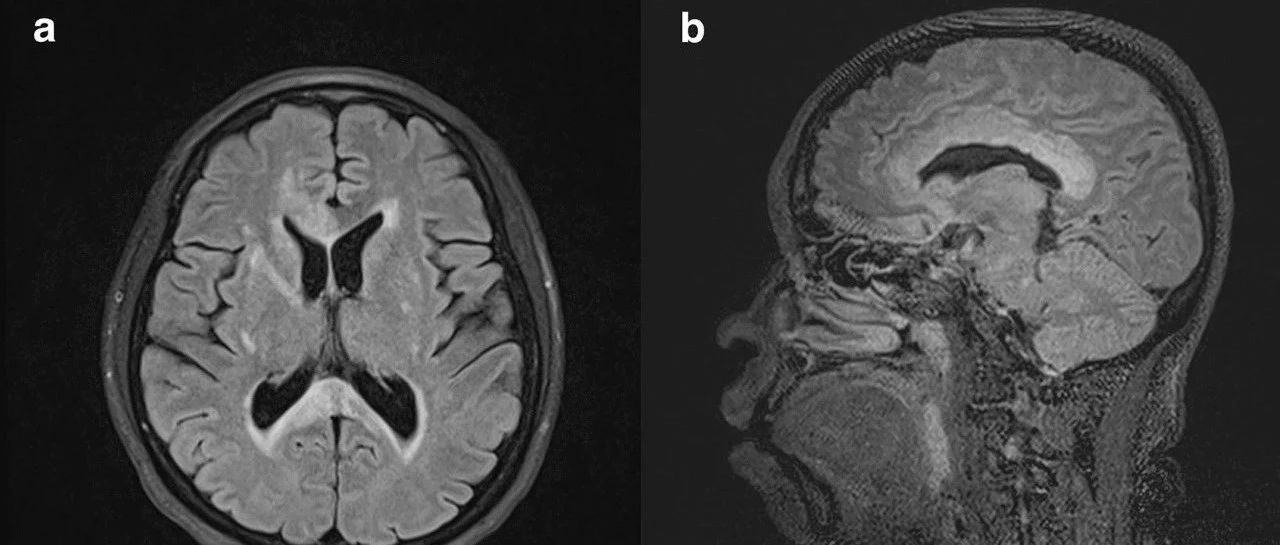

40岁女性,既往体健,突发左侧半身无力和面部不对称2天。查体提示左侧下面部瘫痪和左侧偏瘫,肌力为MRC 2/5级。高级皮质功能和感觉测试正常。没有视觉障碍或结缔组织病的特征。头颅MRI如下:(图:a-b:T2/FLAIR;c-d:DWI/ADC)欢迎投票选择诊断。欢迎在文末评论处分享您的诊断思路。周日公布最终结果。神经病学俱乐部 微信号:NeurologyClub神经病学俱乐部,立足一线临床,服务神经科同行,助力神经病学天天向上...